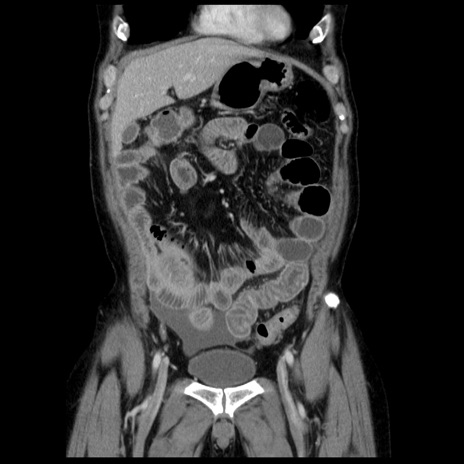

症例29(冠状断像)

【症例】40歳代男性

【現病歴】2日前から胃痛あり。徐々に周期的な激痛に変化した。本日になっても激痛があるため受診。

【身体所見】意識清明、BT 38-39℃台あり、腹部:膨満、やや硬、右下腹部に圧痛あり。

【データ】WBC 8500、CRP 23.26